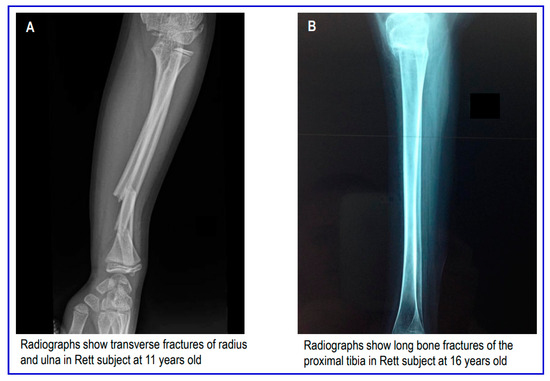

Moreover, in Figure 2, we show typical fractures that occurred in Rett subjects at upper and lower extremities.

Figure 2. Types of fractures in Rett subjects at upper (A) and lower (B) extremities.